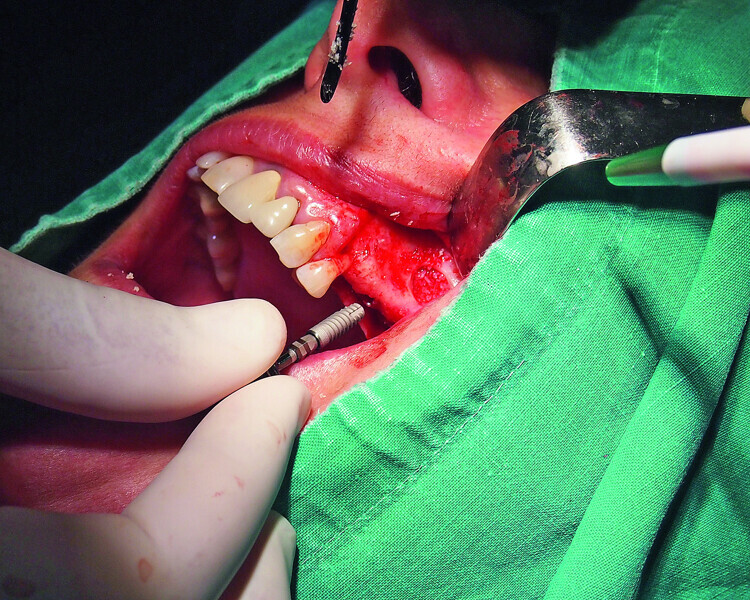

Fig. 7: Placement of a GC Aadva Standard 3.3 x 12.0 mm implant in the premolar region after the sinus graft.